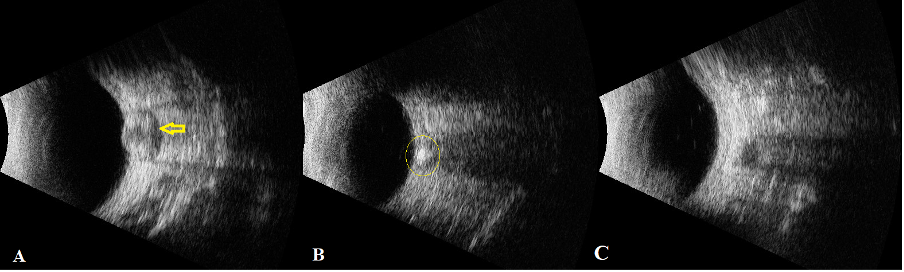

B-scan is performed using a 10MHz probe placed temporally with patient fixing in primary gaze to obtain a transverse section of the optic nerve. The optic nerve is identified as an echolucent tubular structure. It serves the purpose of differentiating papilledema from pseudo disc edema in three ways:

A. Measuring the optic nerve sheath diameter (ONSD)

It is measured at 3mm behind the globe, and any measurement more than 3.3mm can be considered suggestive of papilledema.[9] Yet another study has found a mean of 4.89 (±0.65) mm in cases with papilledema and the diameter correlated positively with the increasing grade of papilledema by Frisen grading.[10]

B. Performing the 30° test

It is performed by measuring the optic nerve sheath diameter in primary position and in 30° abduction. In papilledema, there is a 25% reduction in the ONSD due to the shifting of fluid in the abducted gaze.[11]

C. Identifying the crescent sign

The crescent sign is seen as a hypoechoic shadow within the optic nerve shadow on B-scan and is due to accumulation of fluid in the perineural space, with a sensitivity as good as 92%. [11] However, it may fail in distinguishing true disc edema from optic disc drusen as around only 55% of patients may demonstrate a hyperechoic lesion.[8] When it comes to optic disc drusen (ODD), B-scan reveals a hyperechoic shadow at the optic nerve head with posterior shadowing as shown in Fig 5B.